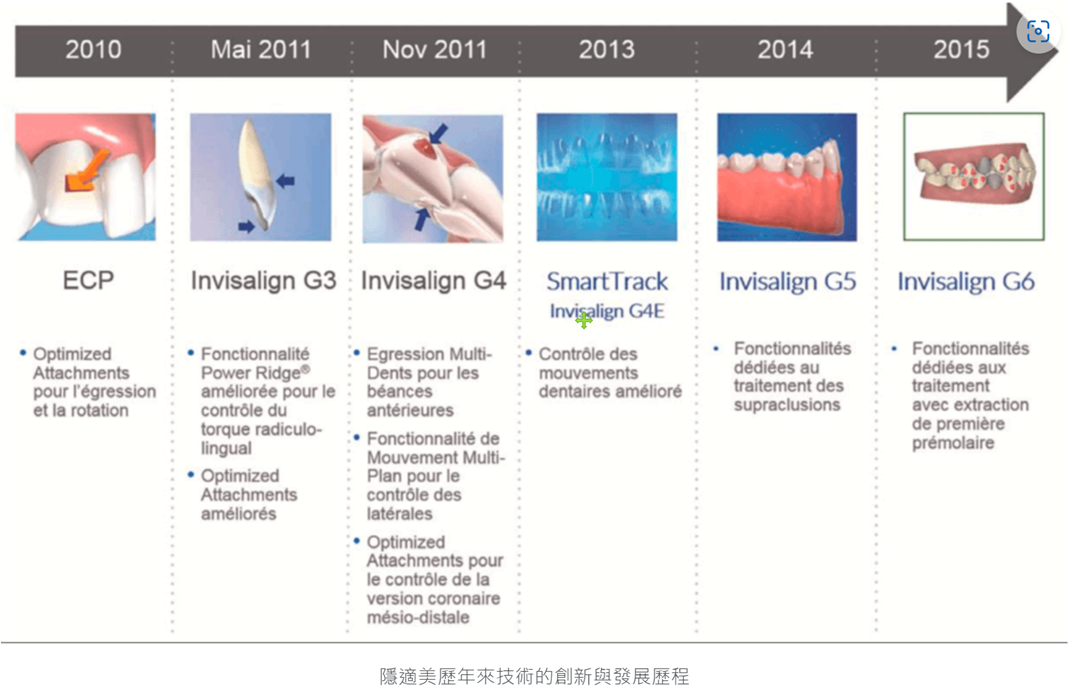

- The second is the maturity of invisible braces technology. In fact, I was exposed to Invisalign in 2011, but the technology at that time could only be limited to treating "slightly messy teeth". In addition, it was expensive and difficult to use. It is convenient (for example, the impressions need to be sent abroad, the travel time is long, etc.), so not many doctors are willing to try it.

- It was only in 2013, when Invisalign Corporation officially established a branch in the Asia-Pacific region, that it began to pay attention to the treatment and research and development of abnormal bites in Asians. The G5 treatment for deep bites in 2014 and the G6 molar extraction treatment in 2015 have slowly begun to attract the attention of doctors in the Asia-Pacific region.

- Regarding the shortcomings of Invisalign discussed in PTT or on the Internet, most of the opinions that Invisalign is only suitable for the correction of slightly messy teeth were made before 2016 (otherwise, the dentist does traditional correction and does not I am familiar with Invisalign and have not kept up with the latest developments). In the past few years, as the technology related to invisible braces has matured, more and more doctors have published treatment methods and improvements for difficult cases. Everyone is constantly optimizing the collected information. Scientific data is used to study treatment patterns for various abnormal bite types, gradually establishing a stable and predictable process.